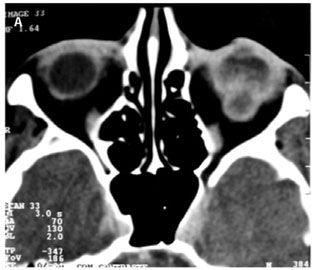

A 54-year-old woman presented to the outpatient ophthalmology department of our hospital in December 2005 with a 7-month history of progressive pain and decrease in vision in her left eye. She had been diagnosed with gastric adenocarcinoma 2 years previously and had undergone total gastrectomy. On presentation, her visual acuity was 20/25 in the right eye and light perception in the left eye. The intraocular pressure was within normal limits in both eyes. There was a relative afferent pupillary defect in the left eye. Anterior segment examination did not reveal any other abnormalities. Fundoscopic examination of the left eye revealed an elevated creamy yellow choroidal tumor infiltrating the macular area and extended around the optic nerve head causing swelling. The vitreous was clear. There was an exudative retinal detachment involving the macula. Ecography disclosed a mass with strong internal echoes in the same region, suggestive of a subretinal tumor. Computed tomography of the orbits demonstrated a large well-circumscribed subretinal mass (Figure 1A). The diagnostic impression on clinical and radiological findings was of a probable metastatic neoplasm. The right eye was unremarkable. Since investigations did not reveal metastasis at any other site, enucleation of the left eye was performed. The histopathological findings of the choroidal metastasis resembled the patient's primary tumor and were consistent with a moderately well-differentiated gastric adenocarcinoma. The patient refused radiation therapy or adjuvant systemic chemotherapy. Eight months after the enucleation, the patient was admitted with intense pain and edema in the left orbit. Computed tomography scan showed a diffuse irregular soft tissue mass involving in the left orbit (Figure 1B). An exenteration of the left orbit was performed without complications and the specimen was submitted to histological evaluation. Histopathological evaluation showed a highly cellular lesion (Figure 2). The cells were predominantly arranged in glands, follicles, and in small clusters and infiltrating tissue planes and vascular structures. On periodic-acid Schiff (PAS) staining, a PAS-positive mucinous secretory material was seen within the gland-like structures. These features were suggestive of a metastatic adenocarcinoma. A systemic work-up revealed multiple retroperitoneal lymph node metastasis and endoscopy showed an irregular narrowing of the esophagojejunal anastomosis, and recurrence of gastric cancer was diagnosed pathologically by biopsy. She was referred to the oncologist for possible palliative therapy. However, she elected not to pursue any form of treatment. The patient subsequently lost follow-up.